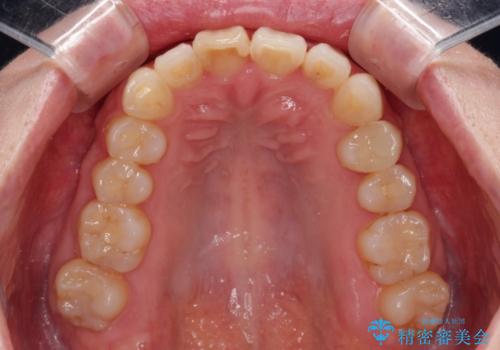

- 上顎前歯の突出感と、前歯のクロスバイトを気にして来院された患者様です。

前歯の叢生と口元の閉じにくさを気にして来院された患者様です。

奥歯の咬み合わせを見ると、上顎が下顎に対して相対的に前方にありました。

口元の閉じにくさを改善するためには、上顎臼歯を後方に移動させた咬み合わせにする必要があります。

インビザライン単体で改善することも可能ですが、達成する可能性が高くないため、カリエールディスタライザーという補助装置を併用して、より確実性を上げることとしました。

奥歯の咬み合わせを改善しながら、並行してインビザラインで歯列を整えることとしました。

カリエール・ディスタライザーを用いたことで上顎前歯の突出感はスムーズに解消され、歯列不正は1年半ほどでほぼ改善することができました。

しかし、その後インビザライン特有の奥歯がうまく噛めないという問題が長引き、改善に1年近い期間を要することとなりました。